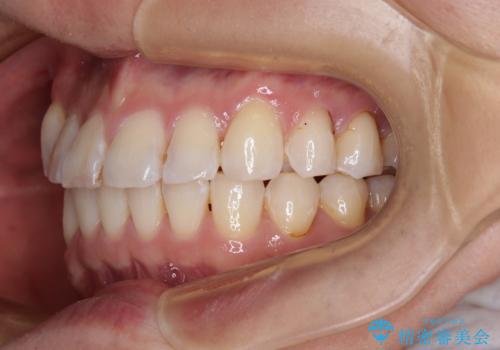

動きにくい歯はやはり動きにくく、咬み合わせ改善に時間を要しましたが、患者様には大変満足していただけました。